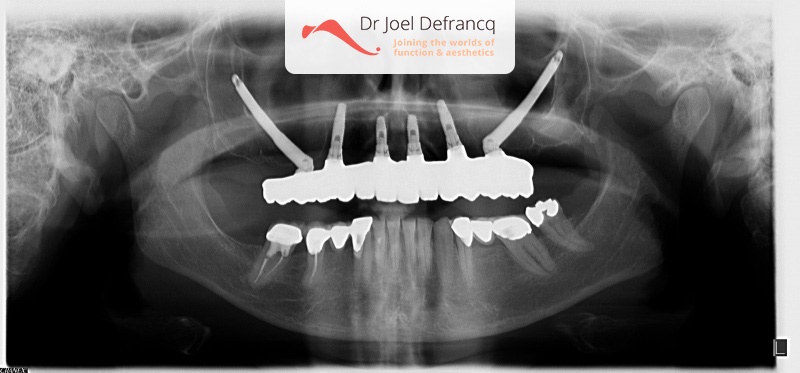

Bij deze patiënten zijn zygoma-implantaten vaak een echt goden-geschenk . Deze implantaten zijn daarom ook eerste keuze. Het ganse proces wordt gerealiseerd in drie tot vier dagen: van de plaatsing van de implantaten tot de plaatsing van de tijdelijke vaste brug in chroom-kobalt-hars met prachtige tanden. We kunnen dit uitvoeren zonder enig esthetische compromis. Raadpleeg voor meer informatie het hoofdstuk op mijn website over zygoma-implantaten.

- De heelkunde: we plaatsen de zygoma-implantaten en meestal ook enkele normale tandimplantaten. Vervolgens nemen we de afdruk.